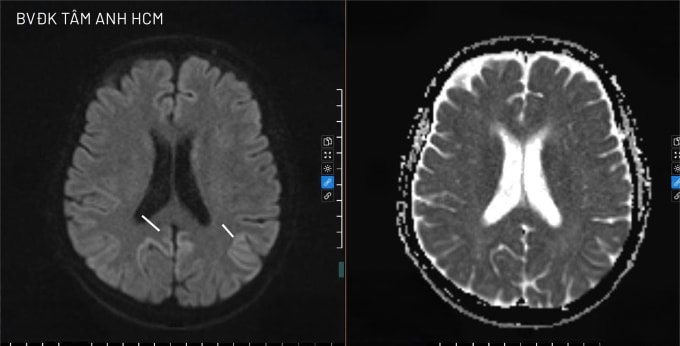

Kết quả chụp MRI 3 Tesla cho thấy nhiều vùng bất thường ở vỏ não và một số cấu trúc sâu trong não. Điện não đồ ghi nhận sóng chậm lan tỏa ở cả hai bán cầu. Bác sĩ chỉ định xét nghiệm dịch não tủy phát hiện protein 14-3-3 tăng cao (82 ng/mL) - dấu ấn sinh học quan trọng giúp củng cố chẩn đoán bệnh liên quan prion.

Ảnh MRI cho thấy vùng vỏ não của ông Tấn tăng tín hiệu dạng "dải sáng" đặc trưng của bệnh Creutzfeldt-Jakob. Ảnh: Bệnh viện Đa khoa Tâm Anh